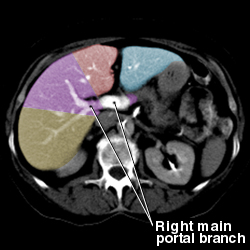

Liver anatomy

Portal Vein:

Segmental Anatomy of Liver